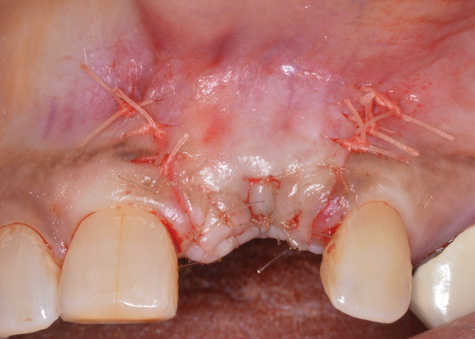

(18.) A subepithelial, connective tissue graft from the palate is affixed over the collagen bone scaffold and around the abutments of the three involved implants.

Figure 18

(19.) At 1-month postoperatively, partial coverage of the exposed abutments/implant platforms has occurred. There is now a band of keratinized mucosa, and the patient is instructed in nontraumatic plaque removal protocols. Follow-up to monitor long-term maintenance of the regenerated keratinized mucosa is encouraged.

Figure 19